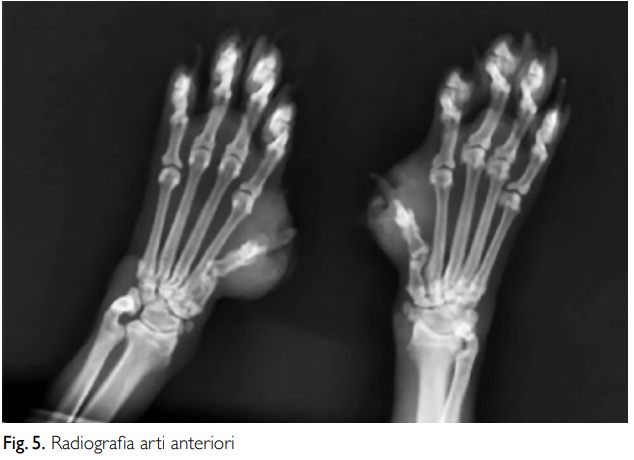

МАТЕРИАЛЫ И МЕТОДЫ КЛИНИЧЕСКОГО СЛУЧАЯ В июле 2017 года на прием была доставлена ОЛЕЗНИ 9-летняя бирманская кошка по кличке Урсула. При осмотре у нее были выявлены множественные очаговые корковые поражения кожи на ушной раковине и переносице, паронихии с отеком третьих фаланг передних и задних конечностей, а также разрозненные пустулы на туловище. ДЕРМАТОЛОГИЧЕСКОЕ ОБСЛЕДОВАНИЕ, проведенное двумя месяцами ранее, 25.05.2017: «Причина обращения: дерматоз. Анамнез: хронический зуд в ушных раковинах и шейно-лицевой области, длящийся более 1 месяца, не поддающийся лечению гипоаллергенной диетой и противопаразитарными препаратами. ЭОП: многоочаговые корковые поражения, расположенные преимущественно на ушных раковинах и переносице. Паронихия с выраженным отеком третьих фаланг кистей и стоп различной локализации. На туловище обнаружено несколько очень маленьких, неповрежденных пустул. Цитологическое исследование: локализация: ногтевое ложе. Внешний вид: казеозный экссудат. Тип образца: соскобы со всех пораженных участков. от паронихии (8 образцов). Описание образца: все исследованные образцы показали отличную клеточность. Были обнаружены многочисленные округлые клетки, иногда с угловатым профилем, центральным ядром и интенсивно базокулярной цитоплазмой, расположенной кластерами или хаотично, наряду с многочисленными недегенеративными нейтрофилы. Цитопатологический диагноз: картина, характерная для листовидного пемфигоида. Ранее назначенное аллопатическое лечение, продолжавшееся на момент обследования (мазь гентамицина сульфата и бетаметазона валерата для местного применения, а также кортизон для приема внутрь), не дало результата, а иногда даже ухудшало состояние. Было решено приостановить текущую терапию и перейти к гомеопатическому обследованию и терапии. Поэтому учитываются не только физические симптомы, но и жизненный контекст животного, предшествующий и семейный анамнез, и, прежде всего, психические и экспрессивные особенности пациента.